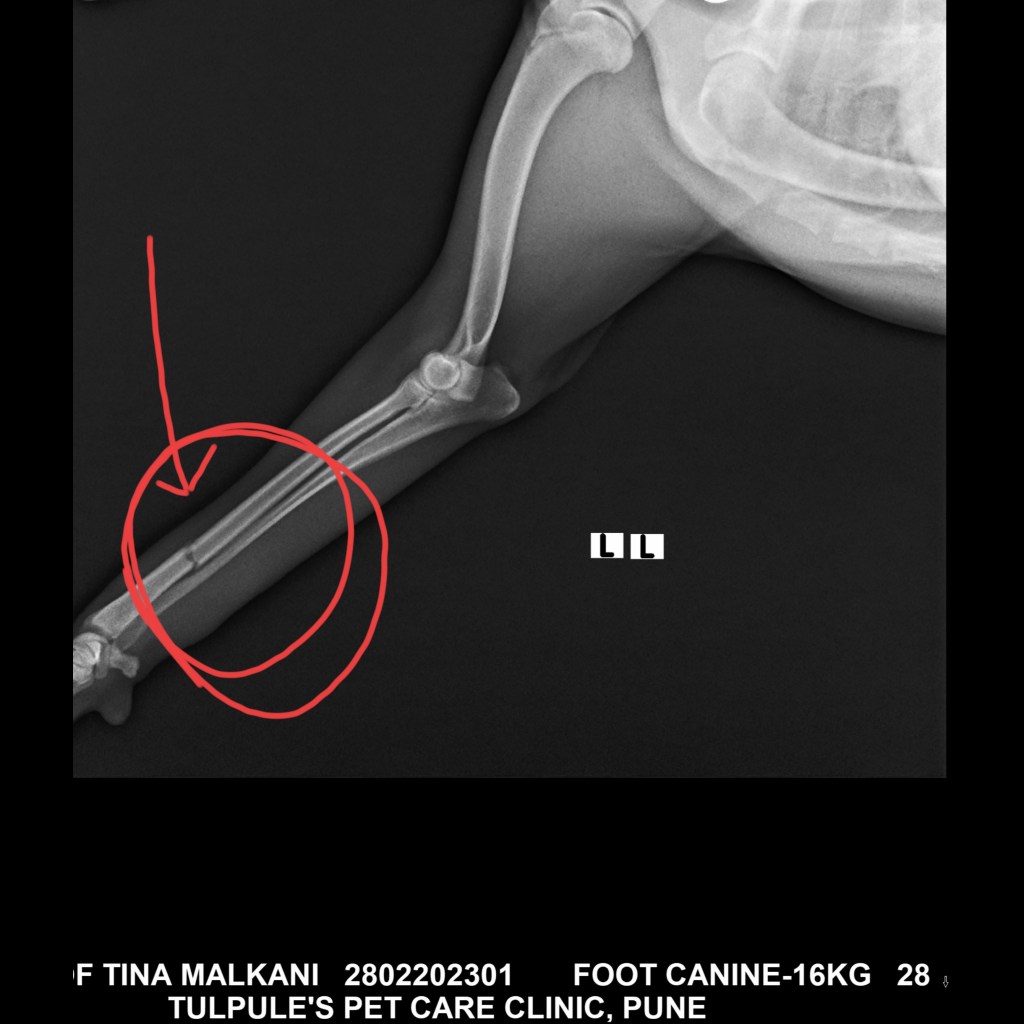

She’s a friendly girl but was very scared since she was in pain and wouldn’t allow us to lift her up. We strategised and somehow with the guards help we managed. Off she went to get an x-ray which revealed that it’s a fracture but luckily it’s not one that will need surgery.

She’s been put in a cast and will need 30 days cage rest . Yes 30 full days. That’s Rs 400*30 🙈..+ transport+ vet fees. (Attached here)